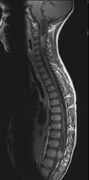

CNS hemangiomas are the most common tumor of VHL, affecting 60% to 80%, with a predilection for the cerebellum and spinal chord. An enlarging cystic component is a frequent finding in symptomatic tumors. Patients typically present in their early 30s; headaches or neck pain in affected individuals should not be ignored.172,173 On microscopy, CNS hemangiomas resemble retinal capillary hemangiomas. Their malignant potential is low.174 The treatment is surgical (Fig. 17, A and B).13

Fig. 17. Images from a 13-year-old boy with Von Hippel-Lindau syndrome. (a) Coronal postcontrast T1-weighted imaging reveals a cystic lesion with an enhancing nodule at the pial surface typical of a hemangioblastoma. (b) A second solid enhancing hemangioblastoma is seen at the craniocervial junction on a sagittal postcontrast T1-weighted image. (c) Associated cystic lesions (arrows) are seen within the pancreas.

Pancreatic lesions may be nonsecretory (most commonly cysts or cystadenomas) or secretory (islet cell tumor).179 In one study of 52 patients, 56% (29 patients) were found to have pancreatic lesions. The majority (19 of 29) had cystic changes only (Fig. 17C). Pancreatic lesions were the only abdominal manifestation of disease in 6 of 52 patients.180 In a separate study, pancreatic cysts did not show significant progression on follow-up examinations over an average period of 5 years.181 Like pancreatic cysts, islet cell tumors appear to be frequently asymptomatic.182